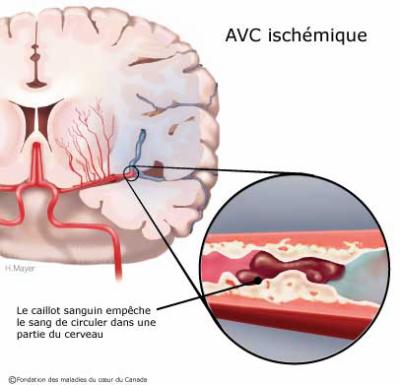

La thrombectomie intracrânienne est une procédure de radiologie interventionnelle réalisée en urgence pour traiter les accidents vasculaires cérébraux (AVC) causés par un caillot de sang qui obstrue une artère du cerveau. Ce type d’AVC est appelé AVC ischémique et constitue environ 80 % des cas d’AVC.

Qu’est ce qu’un AVC ischémique ?

Le plus souvent (80 % des cas), l’arrêt de la circulation du sang est dû à un caillot (ou embol) qui bouche une artère à destination du cerveau. On parle d’AVC ischémique ou encore d’infarctus cérébral.

La cause principale est l’athérosclérose : c’est une accumulation de dépôts de cholestérol sur les parois des artères. Ces dépôts durcissent progressivement et forment des plaques d’athérome qui rétrécissent les artères et favorisent la formation du caillot. Dans certains cas, un fragment de plaque peut aussi se détacher et aller obstruer une des artères à l’intérieur du cerveau.

Parfois, l’accident vasculaire cérébral est la conséquence d’une obstruction d’une artère par un caillot sanguin formé à distance du cerveau, par exemple dans le cœur. Ce caillot est ensuite véhiculé par le sang jusqu’au cerveau. Cela peut survenir notamment en cas de troubles du rythme cardiaque et notamment lorsque le cœur bat rapidement et de manière irrégulière.